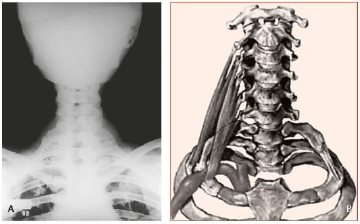

A síndrome compressiva neurovascular incide muito mais frequentemente as mulheres (8:1), geralmente na idade adulta, acarretando sintomas neurológicos, mas também é a causa mais frequente de dilatações arteriais pós-estenóticas (aneurismas). Ao exame físico, pode-se notar uma saliência, sendo que a sua palpação transmite a sensação de “tecla de piano”, descrita como característica dessa anomalia.

Diante do exposto, assinale a alternativa que apresenta a condição descrita no enunciado.